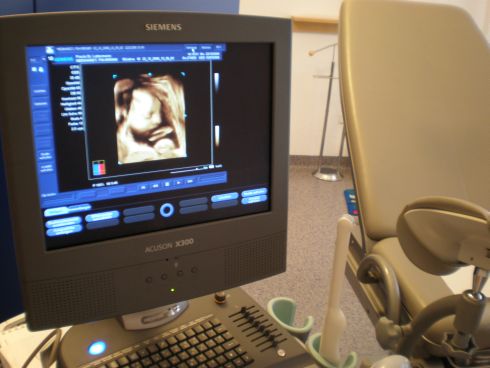

3D / 4D Ultraschall